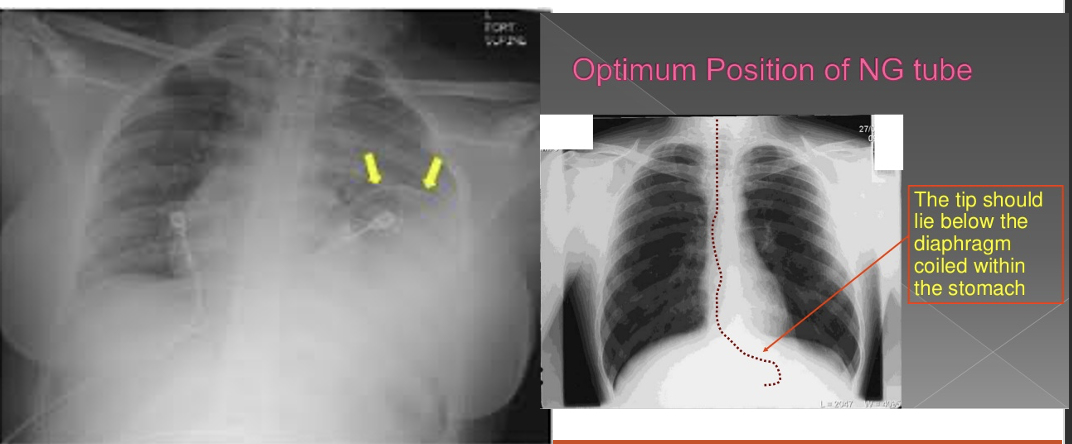

Perforation of the diaphragm is insidious

Bowel sounds in the thorax is diagnostic

Herniation of abdominal contents into thorax

Findings on CXR

NG tube on CXR coiled in the thorax (rare)

MC blurring of the diaphragm or an effusion

Diaphragmatic injury

Diaphragmatic Rupture